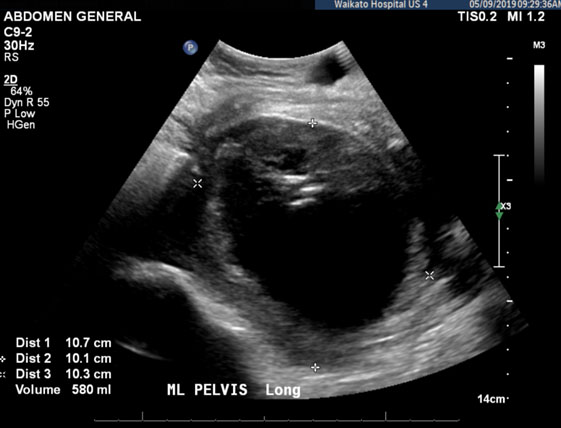

At this stage, both a laparotomy and laparoscopy was offered although she opted for a laparoscopic approach with the hope of reducing her recovery time. Laparoscopy was performed on Day 14 and a large hematoma between the uterus and bladder was identified and drained. No signs of uterine dehiscence or active bleeding were noted. She showed clinical improvement following this, however on Day 24 she became septic with worsening abdominal pain and peritonism on examination. Repeat CT abdomen and pelvis revealed a liquefied rim enhancing BFH extending to the right lower quadrant measuring 13.5 × 12 × 8 cm. As advised by the interventional radiologist, the hematoma was then drained with ultrasound guidance. A drain was left in situ and regularly flushed. Culture grew Staphylococcus aureus and Enterococcus species, however on discussion with infectious disease it was not felt to be consistent with intestinal flora from bowel injury. Three days following this drainage, another ultrasound scan was performed and it showed no change in the size of the collection (Figure 2). The images were reviewed at the gynecology multidisciplinary meeting and the possibility of a small uterine dehiscence contributing to recollection of the hematoma was raised.

Figure 2: Transvaginal ultrasound, longitudinal plane, showing recurrent bladder flap hematoma.